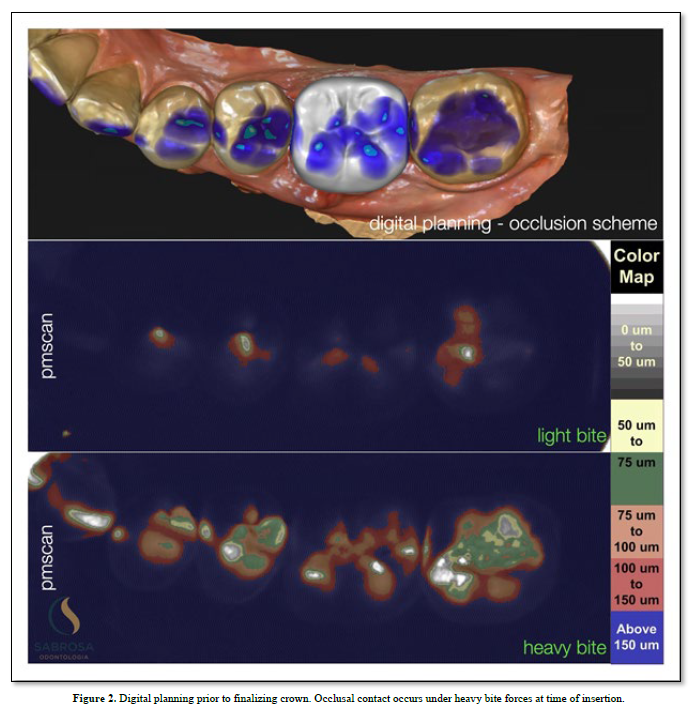

Proprioception is used to navigate space in order for a subject to find a place to make physical contact. (1) An implant with no periodontal housing exhibits little or no proprioception. It has no periodontal housing and no touch or pressure sensors. An opposing functioning tooth with periodontal support is proprioceptive. It is touch sensitive (2). The pressure sensors detect motion and help to reposition and maintain the tooth in a functioning occlusal position. There is little or no information concerning implant proprioception. In a functioning dentition teeth find their position by adjusting to the existing teeth in occlusion. An under occluded implant crown cannot adapt to an existing occlusion without planned occlusal contact guidance. Positional direction and intensity of contact are left to chance. We, as humans, have five senses one of which is touch. Sharks have six senses one of which is touch from a distance (3). Weak electrical signals are used to make contact from afar. Humans can not touch without making physical contact. An implant crown that is under articulated cannot fit into an opposing dentition without making occlusal contact. Total implant placement procedures and restorative healing results are shown (Figure 1). Without implant restorative occlusal contact adjacent teeth and the surrounding dentition adapt to an altered occlusion. Stress distribution is uneven because fewer teeth maintain the occlusal load. Missing limb syndrome where the patient assumes limb retention upon fitting a prosthetic device may be applied to replacing missing teeth where the patient upon tooth replacement immediately assumes past functioning habits. In this case, as shown, tooth and jaw movements related to an altered occlusion are slight but tooth movements are discernible. The occlusal patterns have shifted. There is an uneven amount of occlusal contact upon the second molar (Figure 2). One year later the occlusal contact areas are more evenly distributed. The implant restoration is in functional occlusion. The second molar now fits into the occlusal scheme as does the first molar implant restoration. The teeth have been realigned (Figure 3). In order to plan the occlusion of this implant the clinician (CES) adjusted the surface of the milled zirconia crown (Cerec) prior to completion so that it would just make occlusal contacts upon hard closure (Figure 2). Clinical acumen dictates how much occlusal clearance is required. It is estimated that teeth intrude up to 100 microns upon occlusal loading (3). We assume that when the tooth is fully loaded it will make occlusal contact with its antagonist but when not loaded it will not make contact (4) (Figure 2). To verify contact and non-contact we make a silicone inter occlusal record at the time of insertion (5). The impression is removed and immediately processed using a specially made occlusal scan which includes a direct current light box positioned six inches from an enclosed overhead camera which is connected to an image producing means for recording and interpreting various thicknesses of impression material. The results using image analysis (Image J) can be assessed numerically or viewed using assigned colors that relate to the numbers (6). Two hundred fifty-six pixels is the baseline and the color is white (contact).